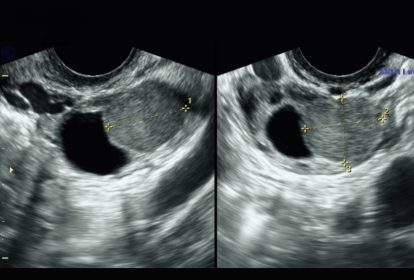

Siêu âm có phát thể hiện lạc nội mạc tử cung bằng việc cho thấy các khối mô lớn hoặc sẹo có khả năng là dấu hiệu của bệnh. Siêu âm có thể xác định bệnh lạc nội mạc tử cung ở buồng trứng nhưng không thể cho thấy các mảnh mô nhỏ (loại lạc nội mạc tử cung phổ biến). Cụ thể, hình ảnh lạc nội mạc tử cung trên siêu âm có thể cho thấy:

- Mô nội mạc tử cung chuyển thành u nang (u lạc nội mạc tử cung), thường gặp nhất ở buồng trứng.

- Mô nội mạc tử cung nằm sâu trong ruột hoặc bàng quang (lạc nội mạc tử cung thâm nhiễm sâu, hay DIE). Những tổn thương này có xu hướng phát triển sâu hơn 5 milimet (mm).

Siêu âm không thể hiển thị mô lạc nội mạc tử cung nhỏ và nằm trên bề mặt của một cơ quan (lạc nội mạc tử cung nông). Các tổn thương nhỏ hơn 5 mm. Đây là loại lạc nội mạc tử cung phổ biến nhất.

Những hình ảnh lạc nội mạc tử cung trên siêu âm

Kết quả sau siêu âm có thể cho ra kết quả bình thường hoặc có vấn đề. Khi có vấn đề siêu âm có thể cho thấy các dấu hiệu của bệnh lạc nội mạc tử cung (như sẹo) hoặc cho thấy u lạc nội mạc tử cung hoặc khối u ruột.